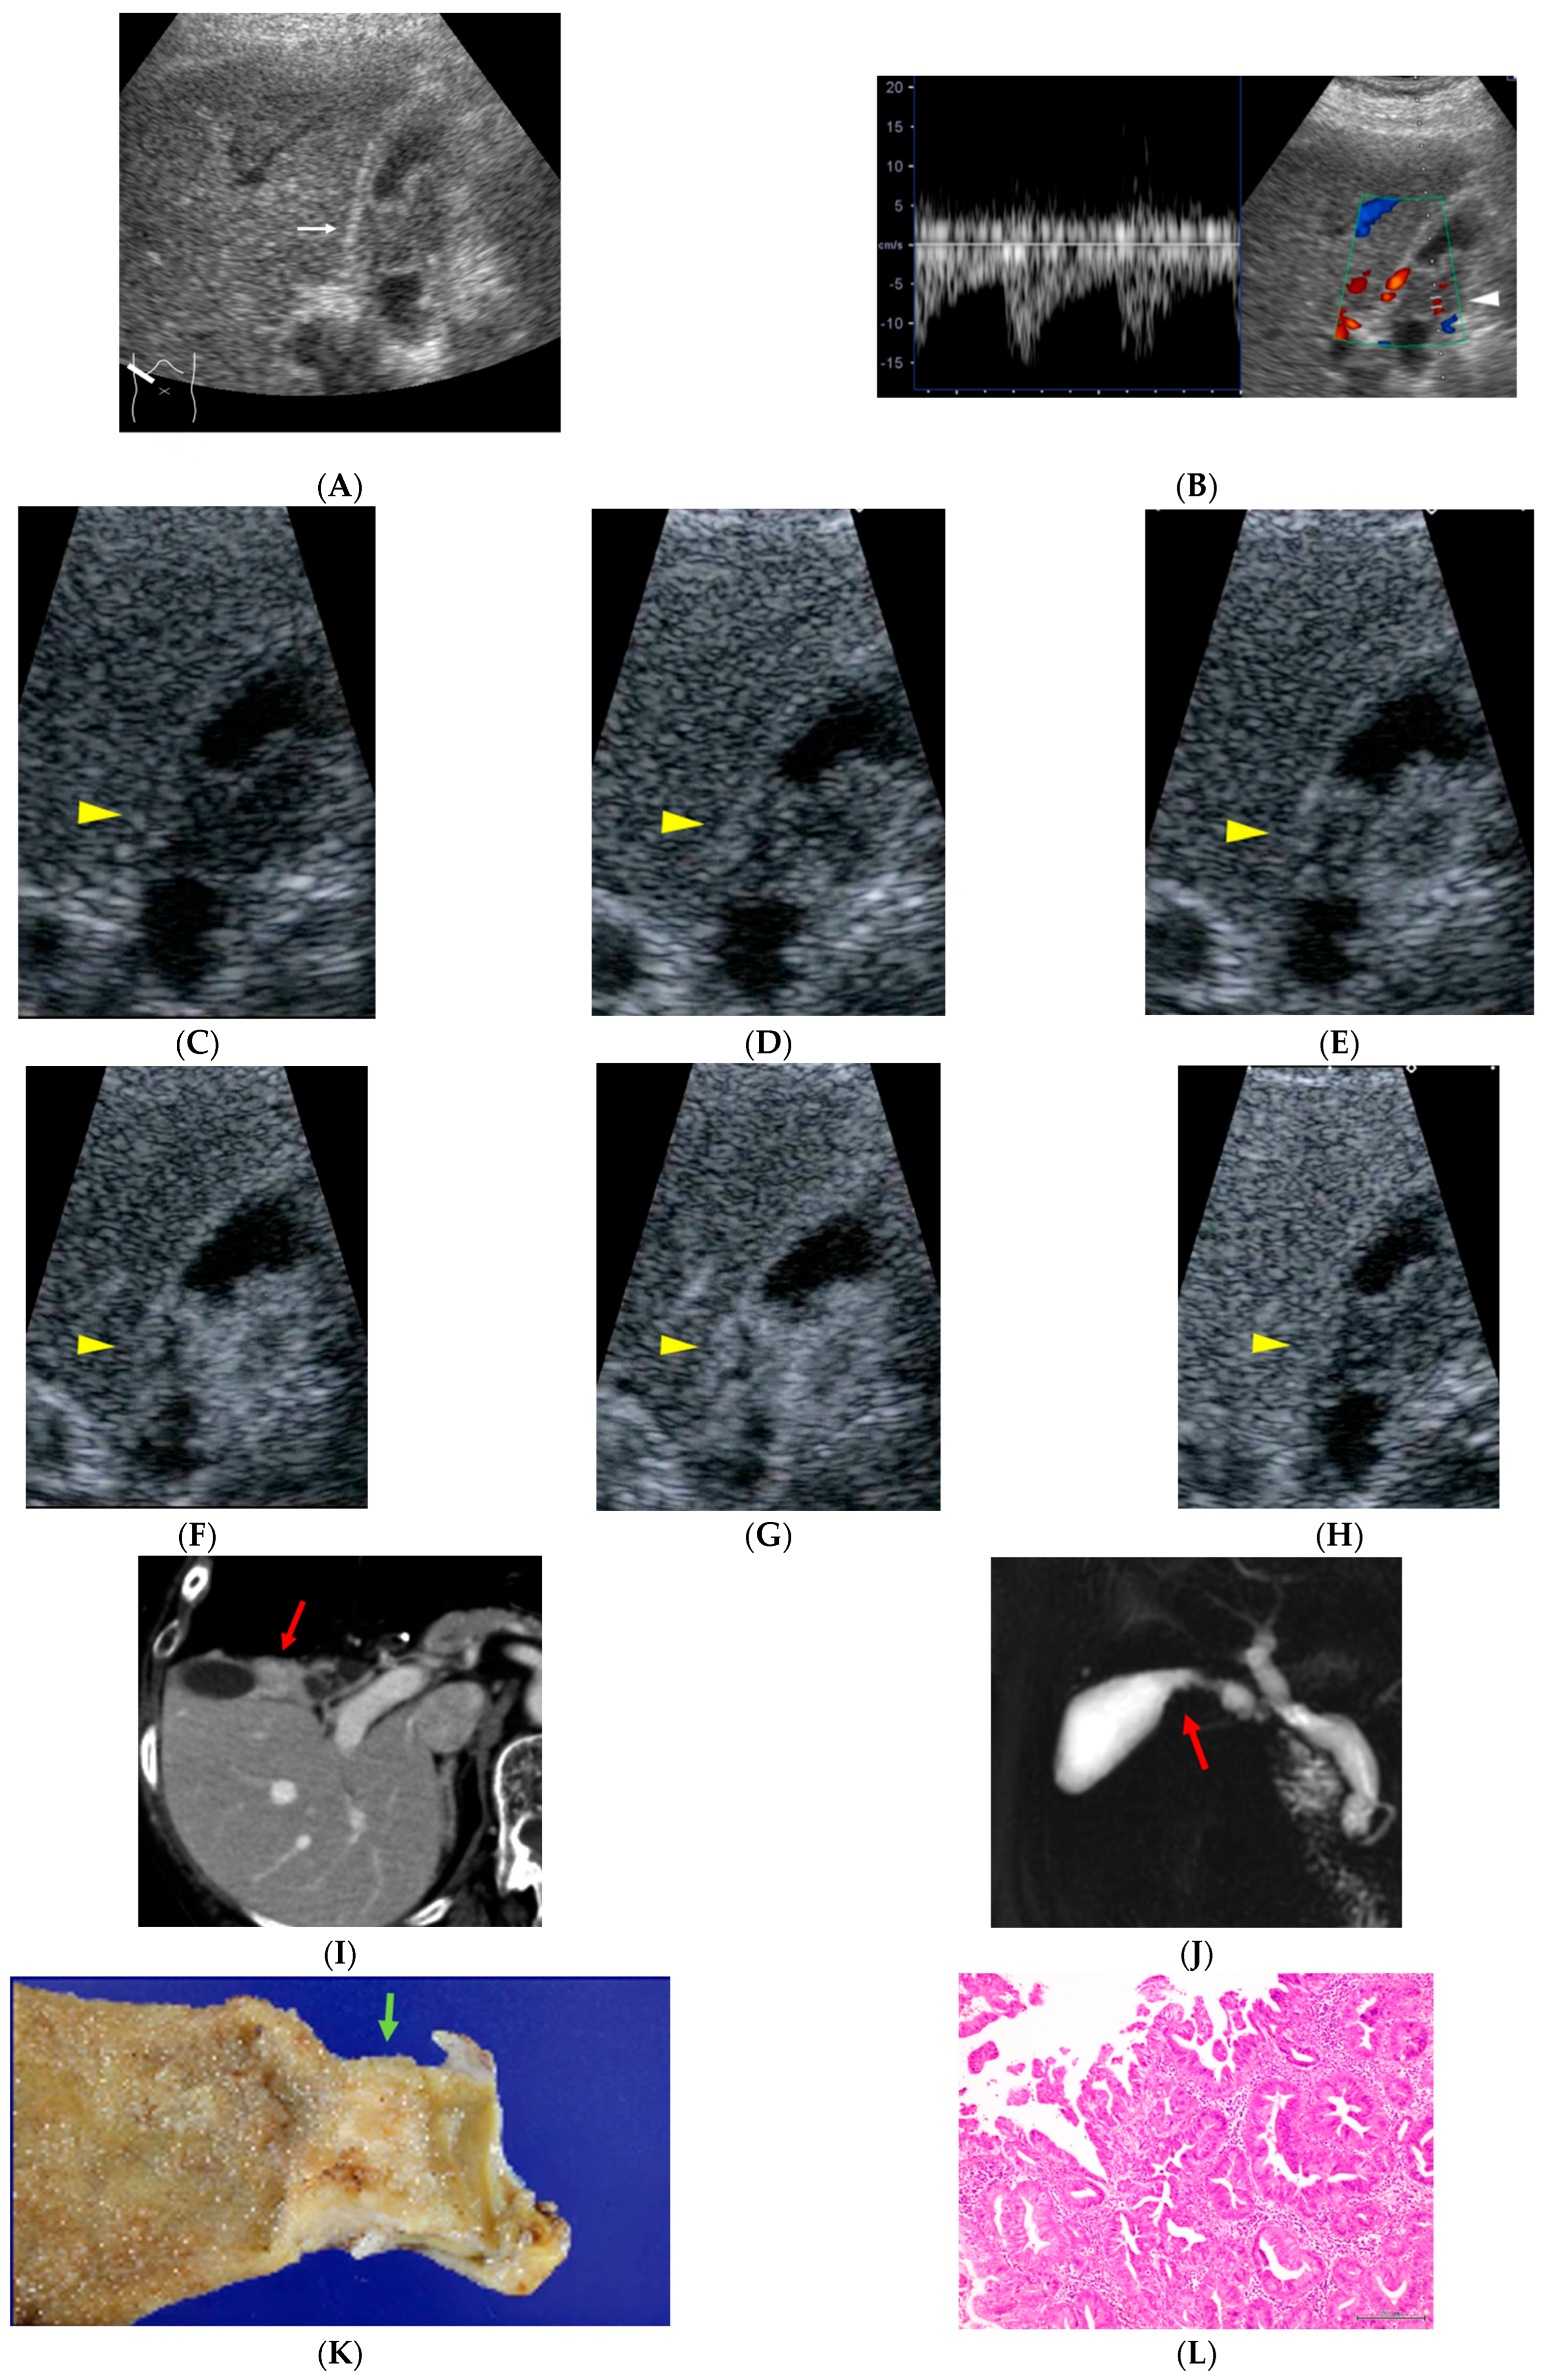

Figure 2.

A 77-year-old woman who had been treated for gastric malignant lymphoma 10 years earlier. During evaluation for abdominal pain, diffuse circumferential wall thickening of the gallbladder body is observed ((A), white arrow). Color Doppler ultrasonography demonstrated pulsatile intratumoral blood flow signals ((B), white arrowhead). On CEUS, the lesion shows early heterogeneous enhancement followed by washout ((C), 0: pre-contrast image; (D), 15; (E), 18; (F), 19; (G), 22; (H), 300 s after injection of contrast material, yellow arrow heads). Contrast-enhanced abdominal CT reveals an enhancing mass lesion at the gallbladder neck ((I), red arrow), and MR cholangiopancreatography demonstrates a corresponding filling defect ((J), red arrow). Histopathological examination confirms papillary adenocarcinoma, stage II ((K), green arrow; (L)). The patient remains recurrence-free for 71 months after surgery.